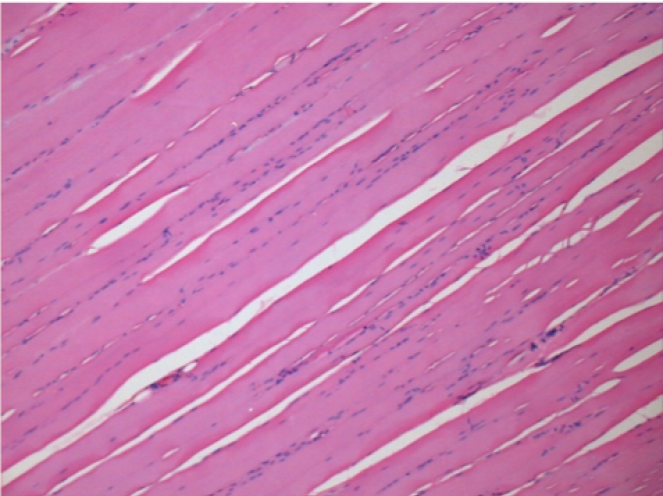

10 days after Endopeel Injection

10 days after Endopeel Injection 0.1ml in the right pretibial muscle.

Here you may see the formation of the vacuoles which are surrounded by lymphocytes. Vacuoles are different from tissue necrosis . The presence of lymphocytes is related to the permeability of the cell membranes.

L : Control-100xD10

R:100xD10

R :200xD10

R :400xD10